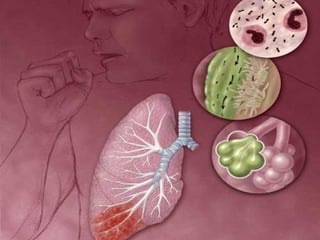

Tuberculose

 Causada pelo bacilo de Koch (Mycobacterium tuberculosis), compromete, em geral, os

pulmões. O doente apresenta tosse persistente, emagrecimento, febre, fadiga e, nos

casos mais avançados, hemoptise (expectoração com sangue).

 As medidas preventivas incluem vacinação das crianças - a vacina é a BCG (bacilo de

Calmet Guérin) - e melhorias dos padrões de vida das populações mais pobres. A infecção

ocorre através de partículas infectantes e o tratamento é feito com antibióticos.

Tuberculose  Principal causade mortes no final do século XIX e início do século XX, segue sendo a infecção mais importante causadora de mortes em adultos no mundo por um único agente infeccioso.  Um dos mais significativos e completos estudos sobre a tuberculose foi realizado pelo alemão Robert Koch (1843-1910).  Em 1927, Arlindo de Assis aplicava pela primeira vez a BCG oral em recém nascidos  Causada pelo bacilo de Koch (Mycobacterium tuberculosis), compromete, em geral, os pulmões. O doente apresenta tosse persistente, emagrecimento, febre, fadiga e, nos casos mais avançados, hemoptise (expectoração com sangue).  As medidas preventivas incluem vacinação das crianças - a vacina é a BCG (bacilo de Calmet Guérin) - e melhorias dos padrões de vida das populações mais pobres. A infecção ocorre através de partículas infectantes e o tratamento é feito com antibióticos.  Estima-se que 1,7 bilhão de pessoas estejam infectadas pelo Mycobacterium tuberculosis, sendo esta doença responsável por cerca de 7% de todas as mortes ocorridas na terra. No Brasil, anualmente ocorrem cerca de 5.000 mortes por tuberculose